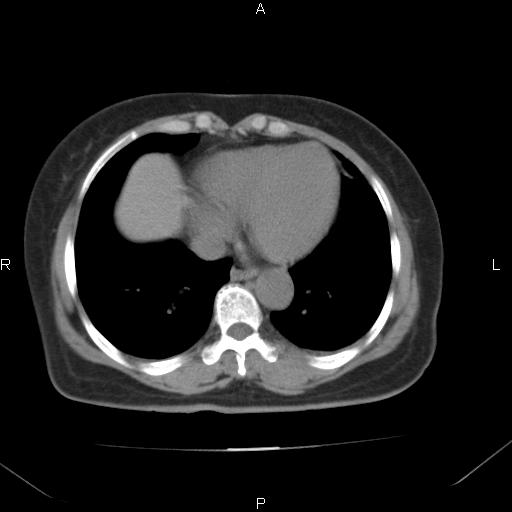

胸腺瘤

女、63Y 双眼睑下垂,早轻晚重。 胸腺瘤???

结果胸腺瘤